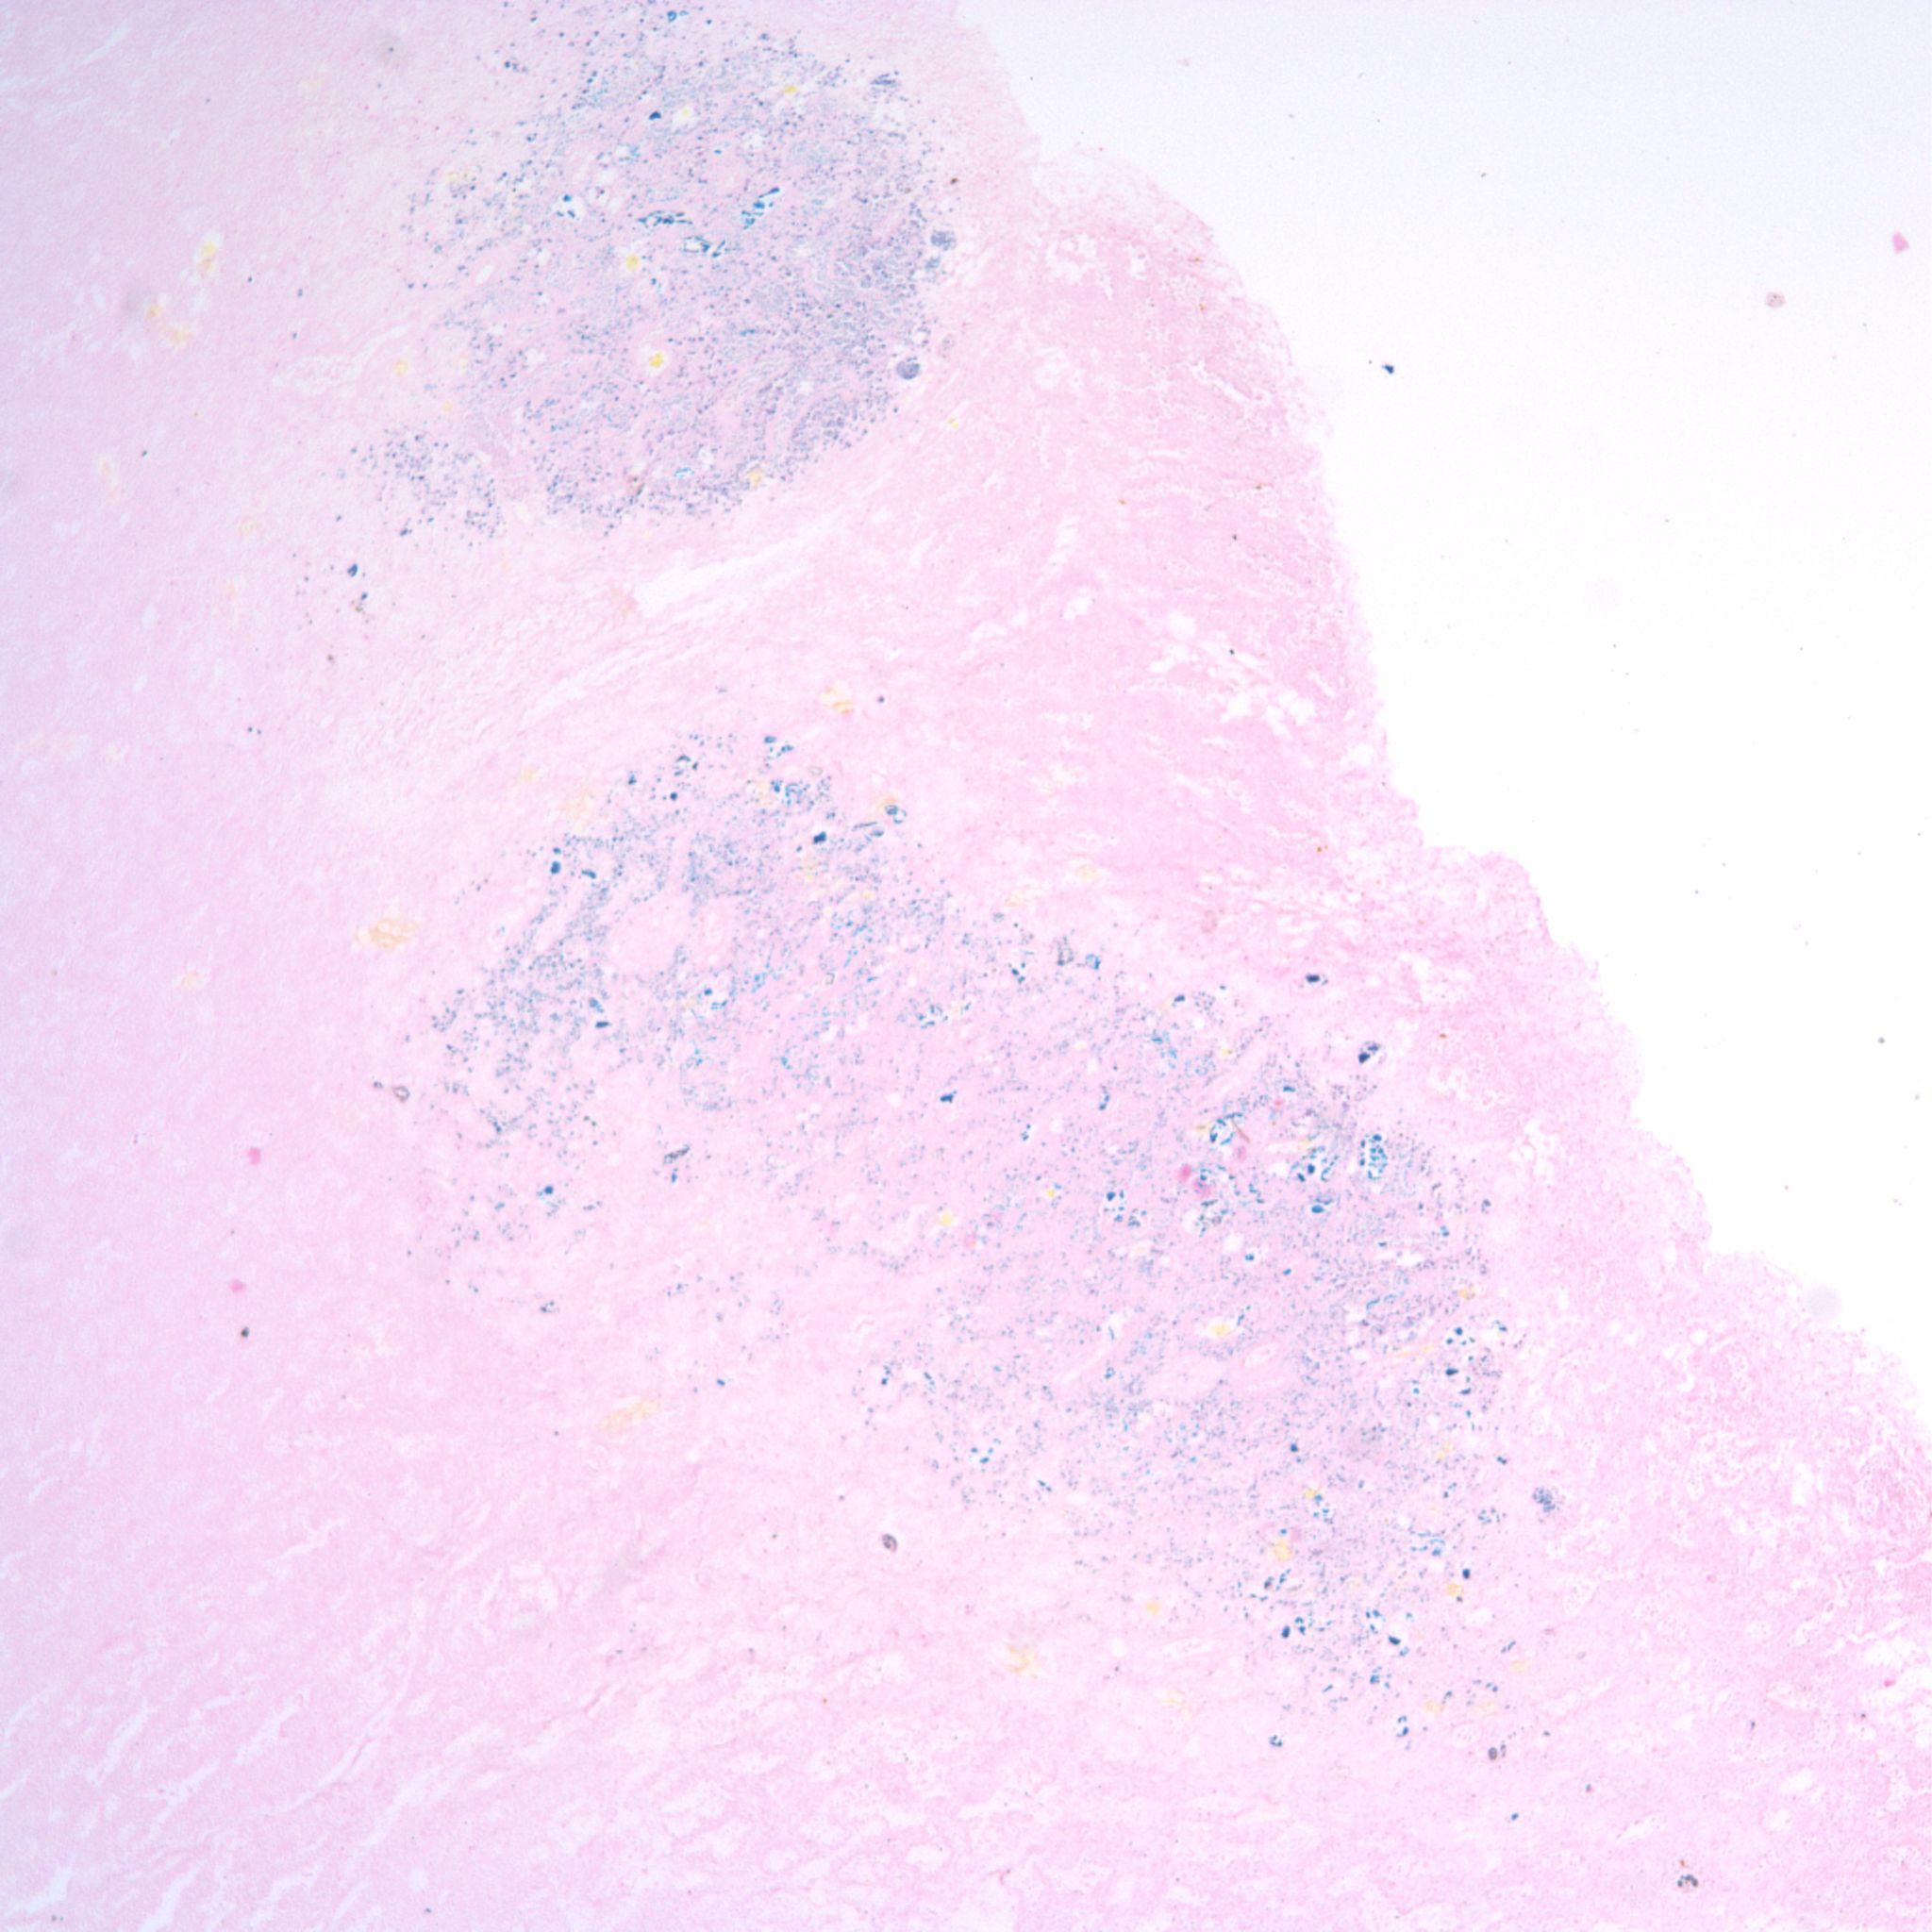

In severely autolytic lung, the distinction between intrinsic hemorrhage and aspirated blood may not be discernable with only iron staining for hemosiderin to trace the vestige of the hemorrhage (Fig 24).